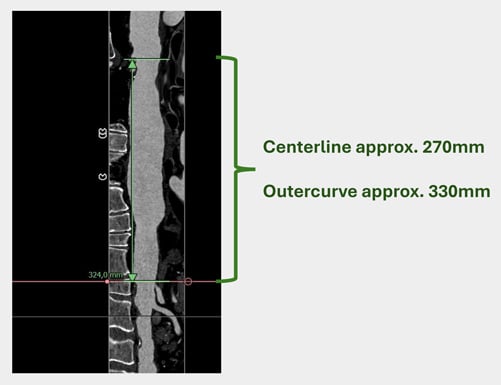

Distal Arch / Proximal descending

Length & extent

Distal landing zone